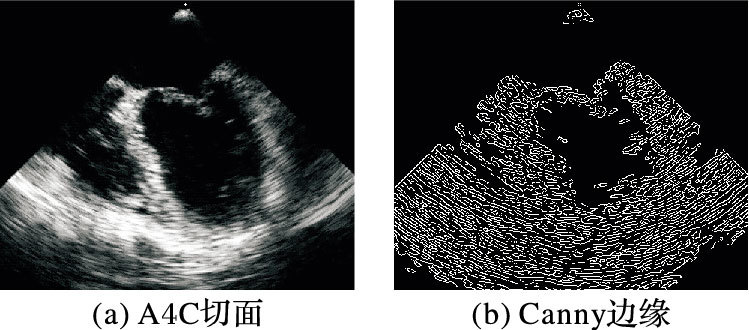

1 基本原理 1.1 各向异性扩散对于一幅B型心脏超声图像,由于超声图像采集设备的采样点有限且采样必须满足Shannon-Nyquist采样定理,B型心脏超声图像存在模糊现象;而且由于成像设备本身的热效应等因素,B型心脏超声图像还存在大量的噪声[13]。同时观察B型心脏超声图像,还可以发现图像会有明暗相间的现象。如图 1(a)是原始B型心脏超声图像的A4C切面,采用Canny算子进行边缘检测的结果如图 1(b)所示。在分割前需要进行预处理去除噪声、平滑区域内部像素。各向异性扩散又叫Perona-Malik扩散,该方法在去除图像噪声的同时能保持图像的重要内容和一些细节信息;实验也证明各向异性扩散方法可以有效地去除噪声,同时增强边缘。

图 1 B型心脏超声图像边缘检测 Figure 1 Edge detection for B-mode cardiac ultrasound image |